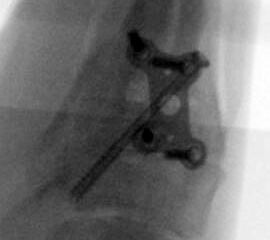

Abbildung 15a

Abbildung 15b

Abbildung 18a

Abbildung 18b

Direkt postoperativ Röntgenkontrolle (Fuß in zwei Ebenen). Sechs Wochen postoperative Röntgenverlaufskontrolle in zwei Ebenen im Stehen. Ist die Überbauung der Arthrodese nicht gut zu beurteilen, kann eine ergänzende 45° Supinationsaufnahme des Fußes angefertigt werden, die einen guten Einblick in das Tarsometatarsale-I-Gelenk ermöglicht.